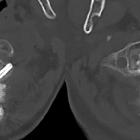

Behandlung

einer instabilen Densfraktur: Spondylodese HWK 1 / 2 mit dorsalem Fixateur interne. Die Pedikelschrauben sind gekreuzt eingebracht. Der hintere Atlasbogen wird von den Klammern umfasst. Zusätzlich Spongiosamaterial angelagert.